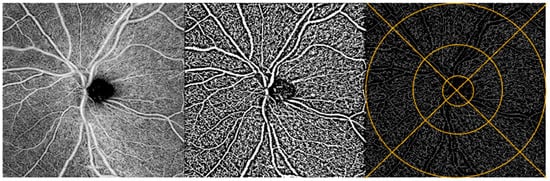

The Fiji application of ImageJ (NIH, Bethesda, MD, USA) was used to process the OCTA images. Based on the literature support and extensive subjective quality assessments of the Phansalkar, Niblack, and Otsu local binarization methods, we selected the Phansalkar method for macula images and Niblack for the ONH images [29,30,31]. Next, binarized images were skeletonized, making each vessel 1 pixel wide to assess capillary density and to minimize the effect of larger vessels on vessel density.

ONH: Vessel density. We assessed the full retinal thickness and superficial vascular plexus captured in the 6 × 6 mm2 ONH angiograms. We did not assess the deep vascular plexus due to poor image quality. The Early Treatment of Diabetic Retinopathy Study (ETDRS) grid was overlaid to allow regional analysis in 4 quadrants divided into inner and outer parts, for a total of 8 regions: inner superior, outer superior, inner nasal, outer nasal, inner inferior, outer inferior, inner temporal, and outer temporal (Figure 2) [32]. The ETDRS grid was manually centered over the ONH using the translate function within ImageJ to ensure alignment of the grid and the image. Two individuals analyzed the ONH data. They were trained on a dataset of 5 images prior to analyzing all of the images. The coefficient of variation between the two graders’ manual centering of images was 0.0057 (ICC(2, 1) = 0.9996)). Data included vessel density values for all 8 regions, as well as the average vessel density across the 8 regions.

Figure 2. ONH image analysis. OCTA image of the ONH region of a participant’s retina (left). Same OCTA image with Niblack binarization applied (middle) and with binarization + skeletonization applied (right). Example of ETDRS grid overlay on skeletonized image (right).